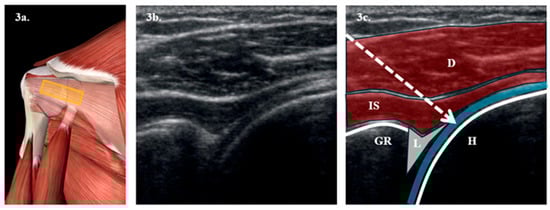

- Firstly, an ultrasound-guided SSNB will be performed with 4 mL of 0.25% bupivacaine + 0.5 mL of triamcinolone acetonide in the suprascapular notch. Figure 2.

Figure 2. Illustration of access point for performing SSNB via posterior route: (a) Anatomical representation of the scapular fossa seen from a posterior view, obtained from Essential Anatomy 5 after removing the trapezius muscle plane. The yellow rectangle represents the probe position. (b) Longitudinal ultrasound section with a 6–15 MHz linear probe of the suprascapular fossa. (c) Representation of the most notable anatomical structures in the suprascapular fossa. The foreground corresponds to the trapezius (T), followed by the supraspinatus (SS) muscle. Below, the transverse ligament (TL), which forms the roof of the scapular notch (SN), appears. Below the TL, the suprascapular nerve (N), represented by a yellow circle, appears; and above, the suprascapular vein (V) and artery (A) appear represented by a blue and red circle. - -